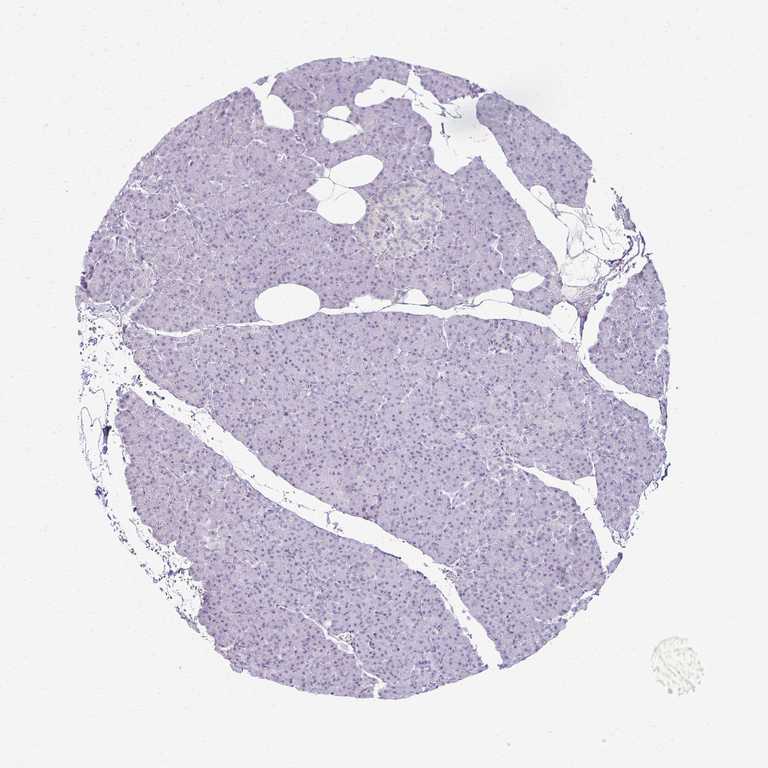

PANCREAS - Antibody stainingi

Antibody staining in the annotated cell types in the current human tissue is reported as not detected, low, medium, or high, based on conventional immunohistochemistry profiling in selected tissues. This score is based on the combination of the staining intensity and fraction of stained cells.

Each image is clickable and will lead to virtual microscopy that enables deeper exploration of all samples and also displays staining intensity scores, fraction scores and subcellular localization as well as patient and tissue information for each sample.

Antibody HPA061223

Exocrine glandular cells Low

Pancreatic endocrine cells Not detected